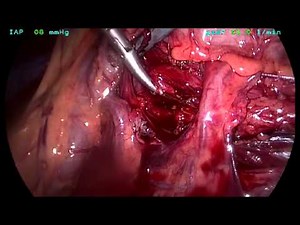

- Pyeloplasty

Procedure - Robotic

Pyeloplasty - Robotic Pyeloplasty

Pyeloplasty